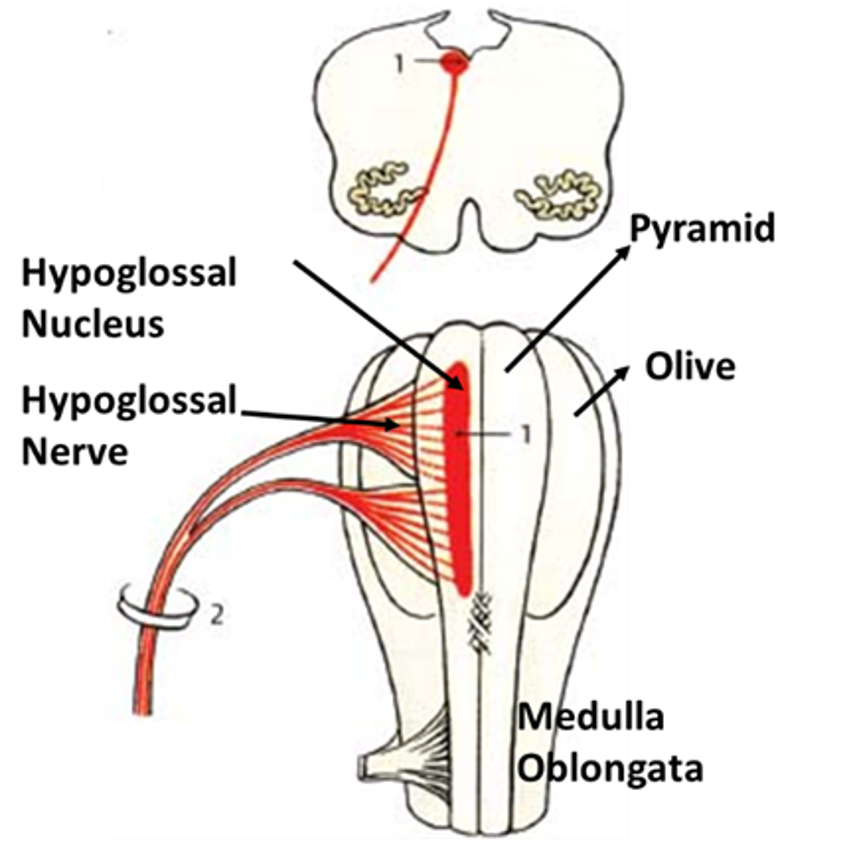

Hypoglossal Nerve Intermedullary Course

Hypoglossal Nerve Intermedullary Course

Neuroanatomy, Cranial Nerve 12 (Hypoglossal) – StatPearls – NCBI Bookshelf